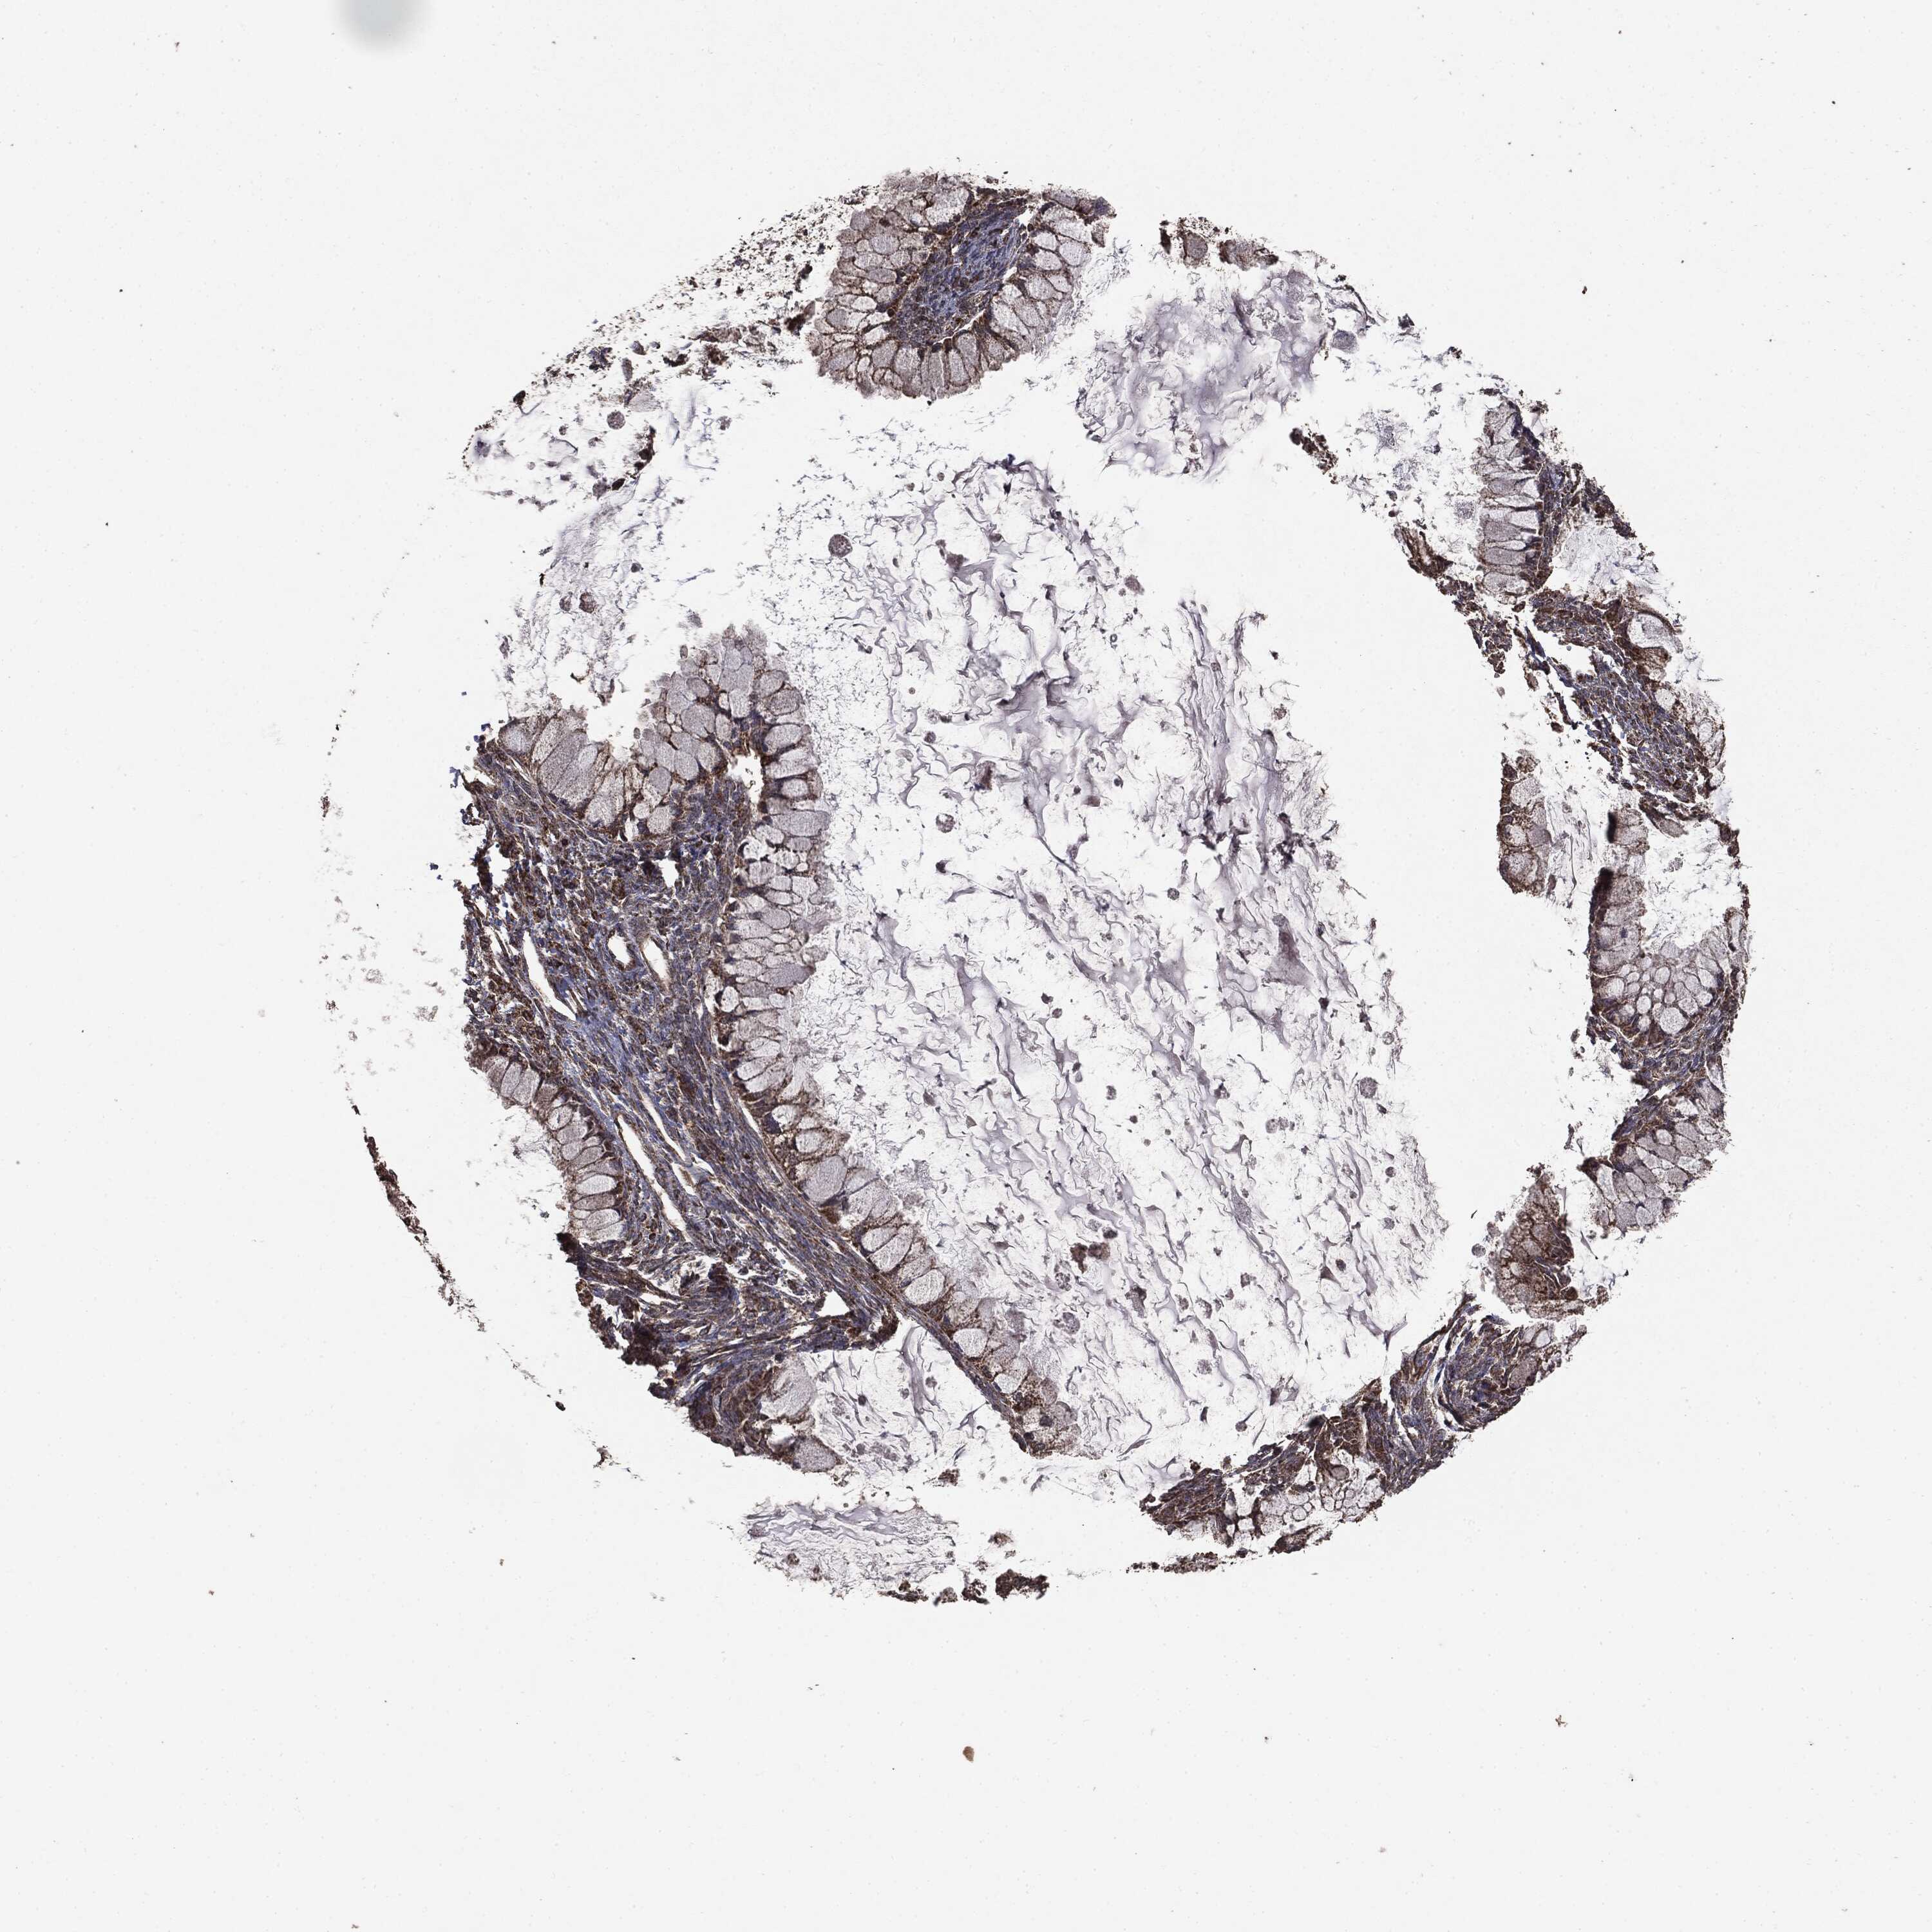

OVARIAN CANCER - Protein expressioni

A mouse-over function shows sample information and annotation data. Click on an image to view it in a full screen mode. Samples can be filtered based on level of antibody staining by selecting one or several of the following categories: high, medium, low and not detected. The assay and annotation is described here.

Note that samples used for immunohistochemistry by the Human Protein Atlas do not correspond to samples in the TCGA dataset.

Antibody stainingi

Antibody staining in the annotated cell types in the current human tissue is reported as not detected, low, medium, or high, based on conventional immunohistochemistry profiling in selected tissues. This score is based on the combination of the staining intensity and fraction of stained cells.

Each image is clickable and will lead to virtual microscopy that enables deeper exploration of all samples and also displays staining intensity scores, fraction scores and subcellular localization as well as patient and tissue information for each sample.

Cystadenocarcinoma, mucinous, NOS